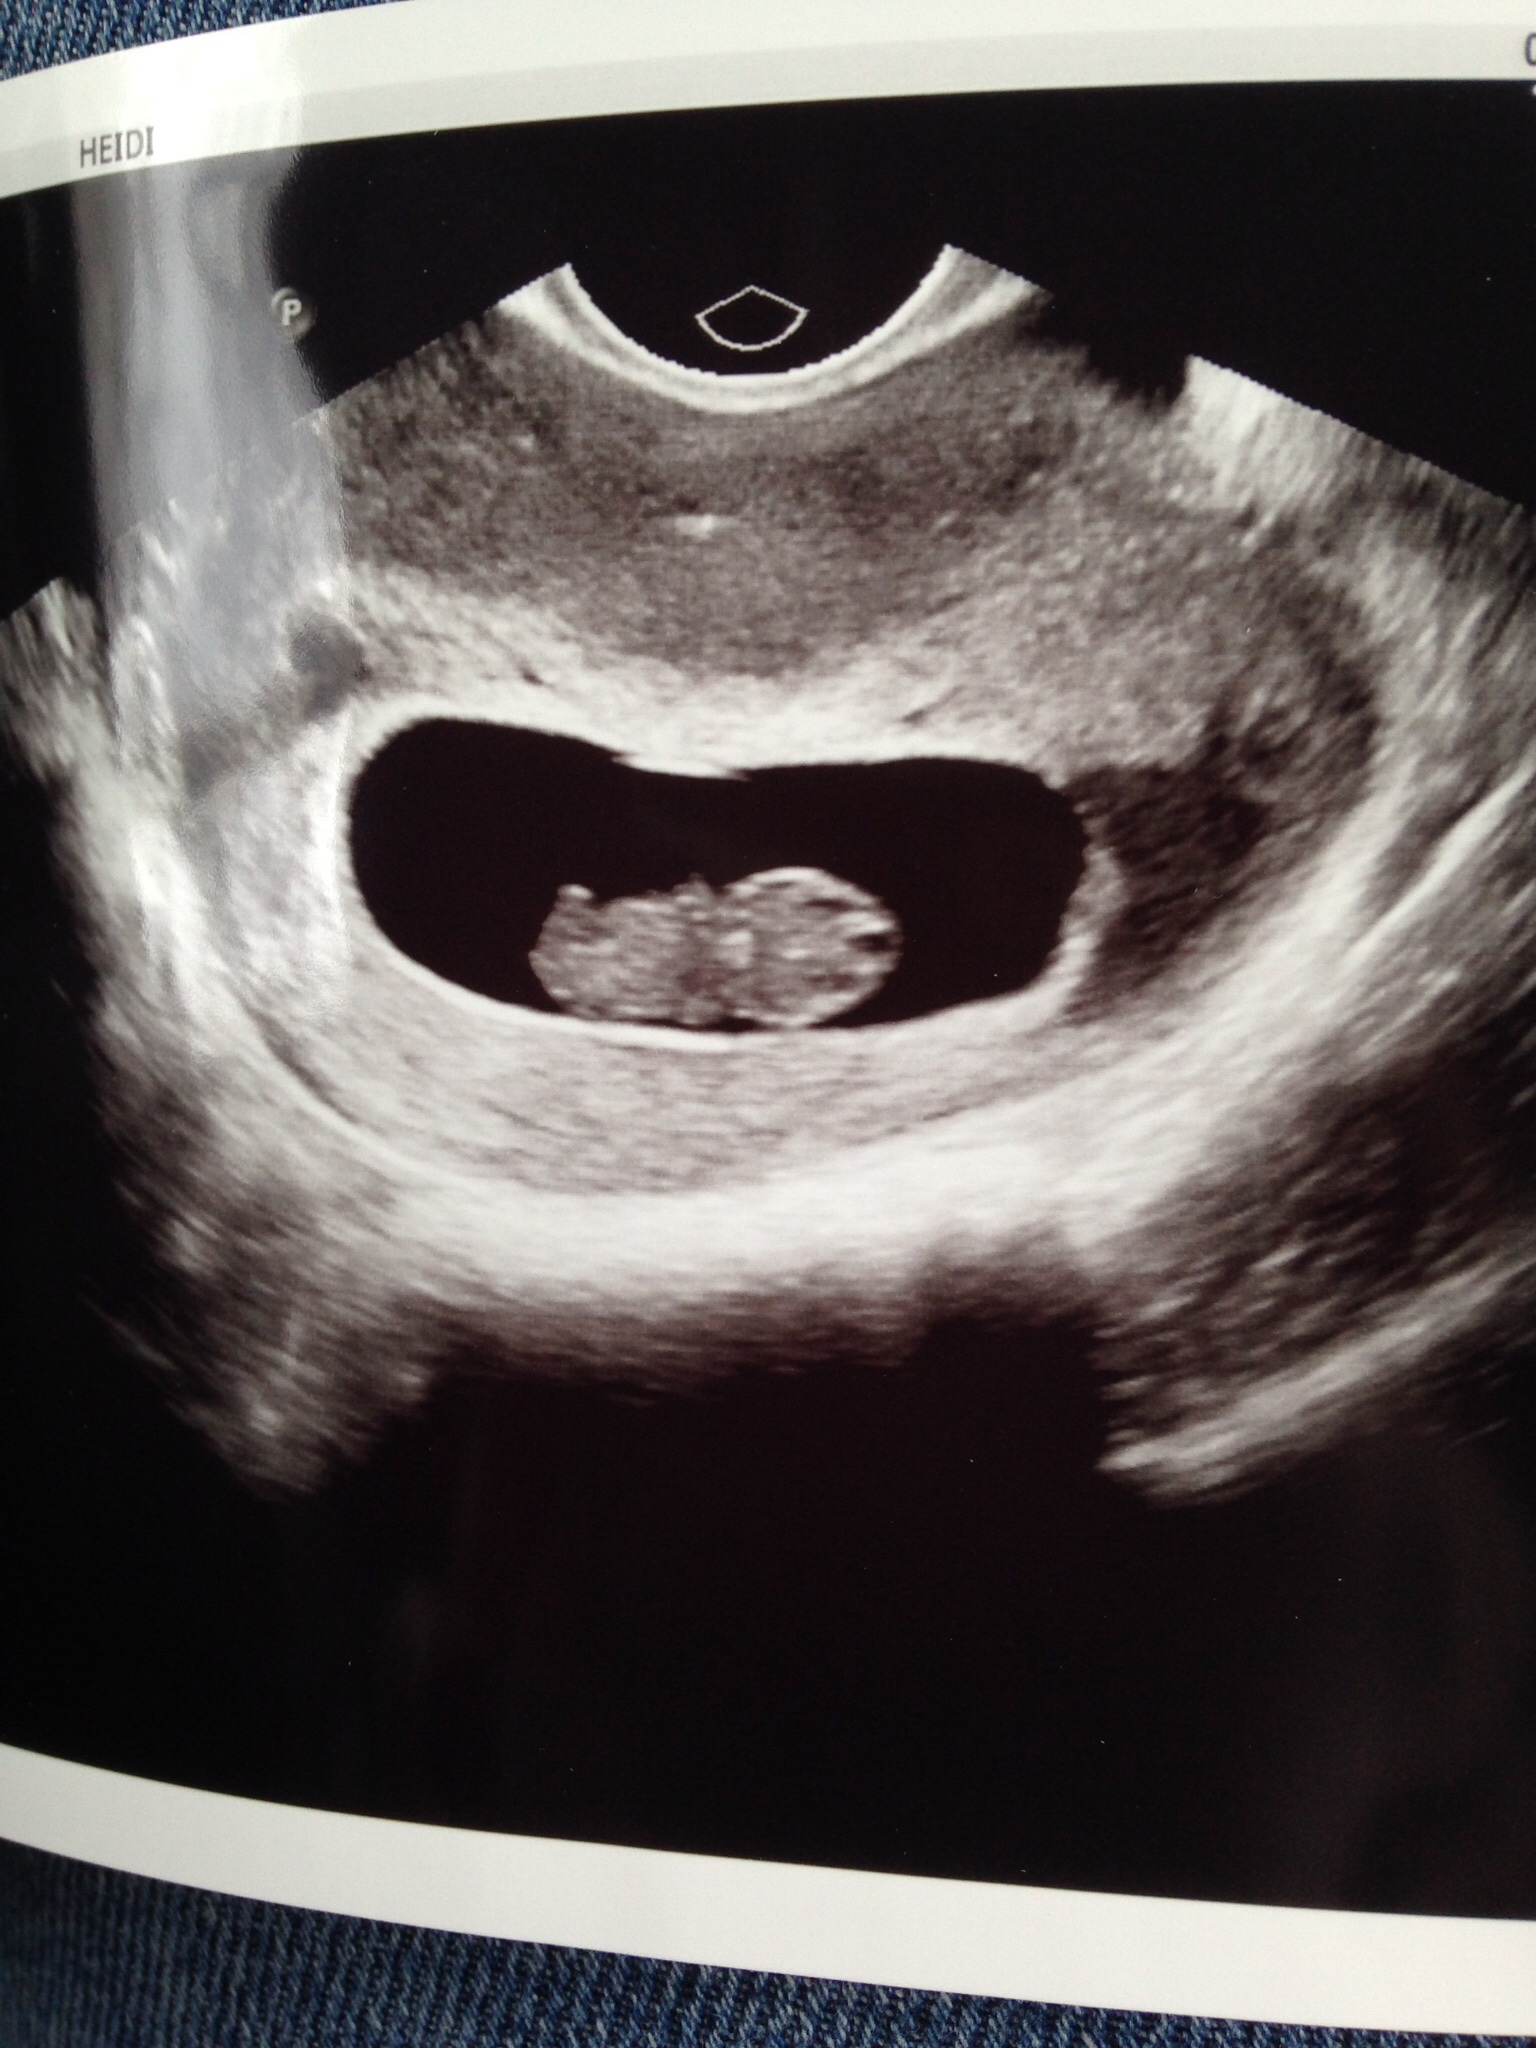

I was 8 weeks 5 days in this ultrasound, transvaginal.

Please give me some guesses!!! Attachment 30963